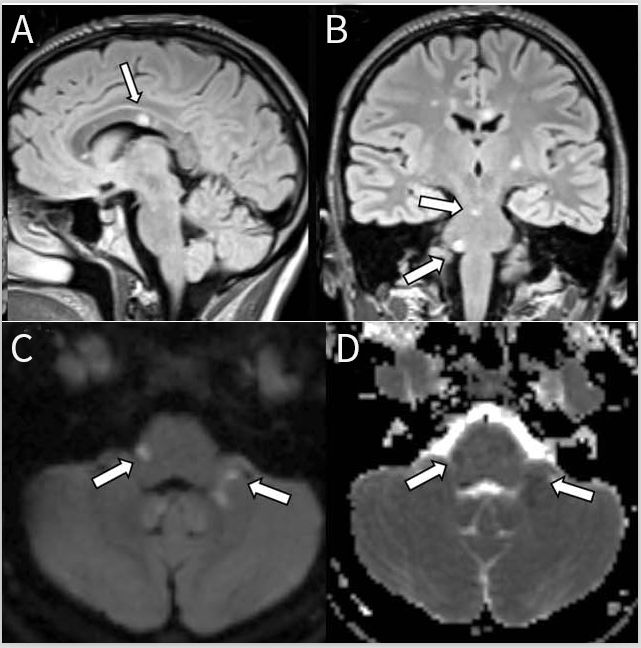

图4 神经结节病患者的MRI影像。轴位T1增强(A,C)和FLAIR序列(B),冠状位T1增强(D,E)显示整个脑干点线状病变并延伸到小脑脚和白质,所有病灶在T 1增强上比T2或FLAIR序列更明显。

图7 朗格汉斯细胞组织细胞增生症患者MRI影像。轴向FLAIR(A)显示脑桥和邻近的小脑半球弥漫性和不均匀性高信号,呈斑驳的外观。轴位(B)和冠状位(C)T1增强图像可见脑桥病灶呈斑点状强化。